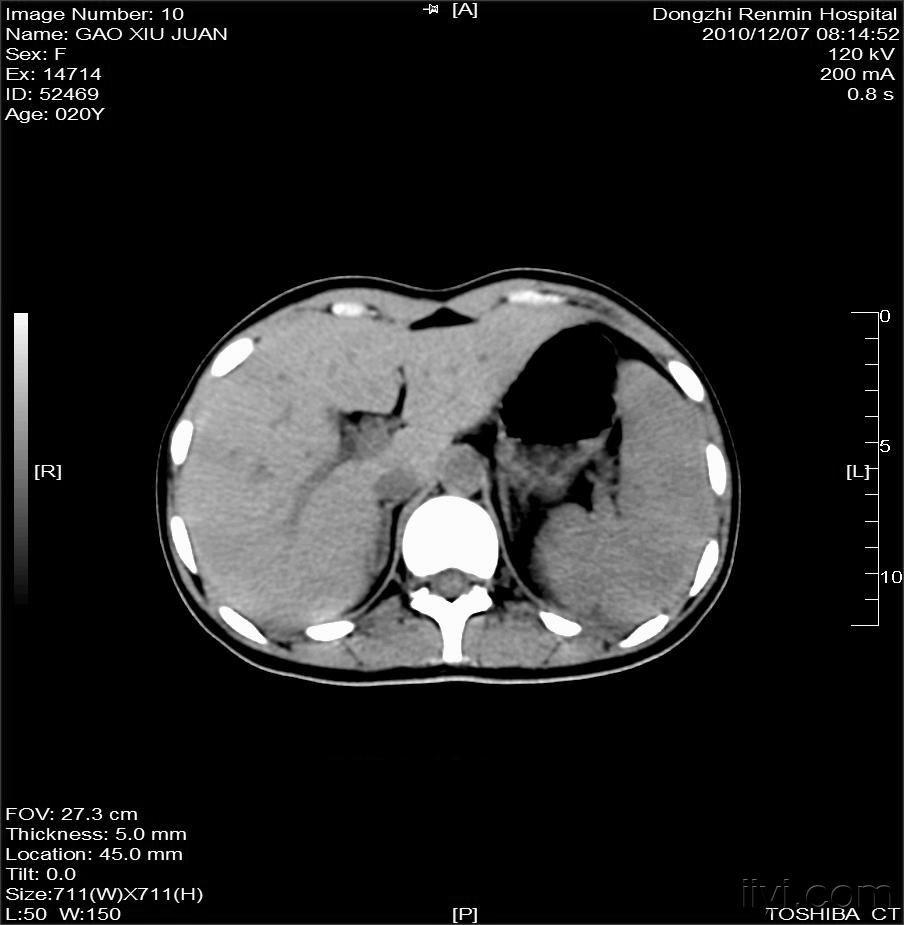

23 mm*21 mm,增强后中间部分无强化,周围中度强化,边界欠清,肾脓肿